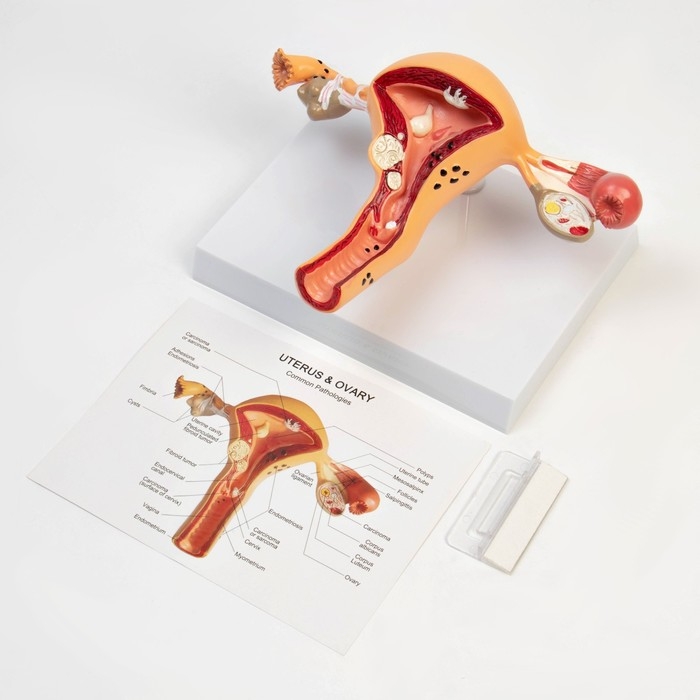

ЕКБ 39

No Brand, артикул: 7072361